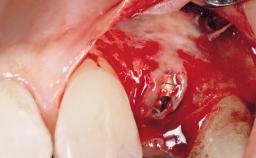

Immediate Flapless Placement of an Implant in a Maxillary Left Central Incisor Site

| Placement Protocol | Immediate implant placement |

| Tooth Site | Maxillary incisor or canine |

| Socket Morphology | Single-root socket |

| Socket Integrity | Damage to one or more bone walls |

| Bone Volume | Damage to one or more socket walls |